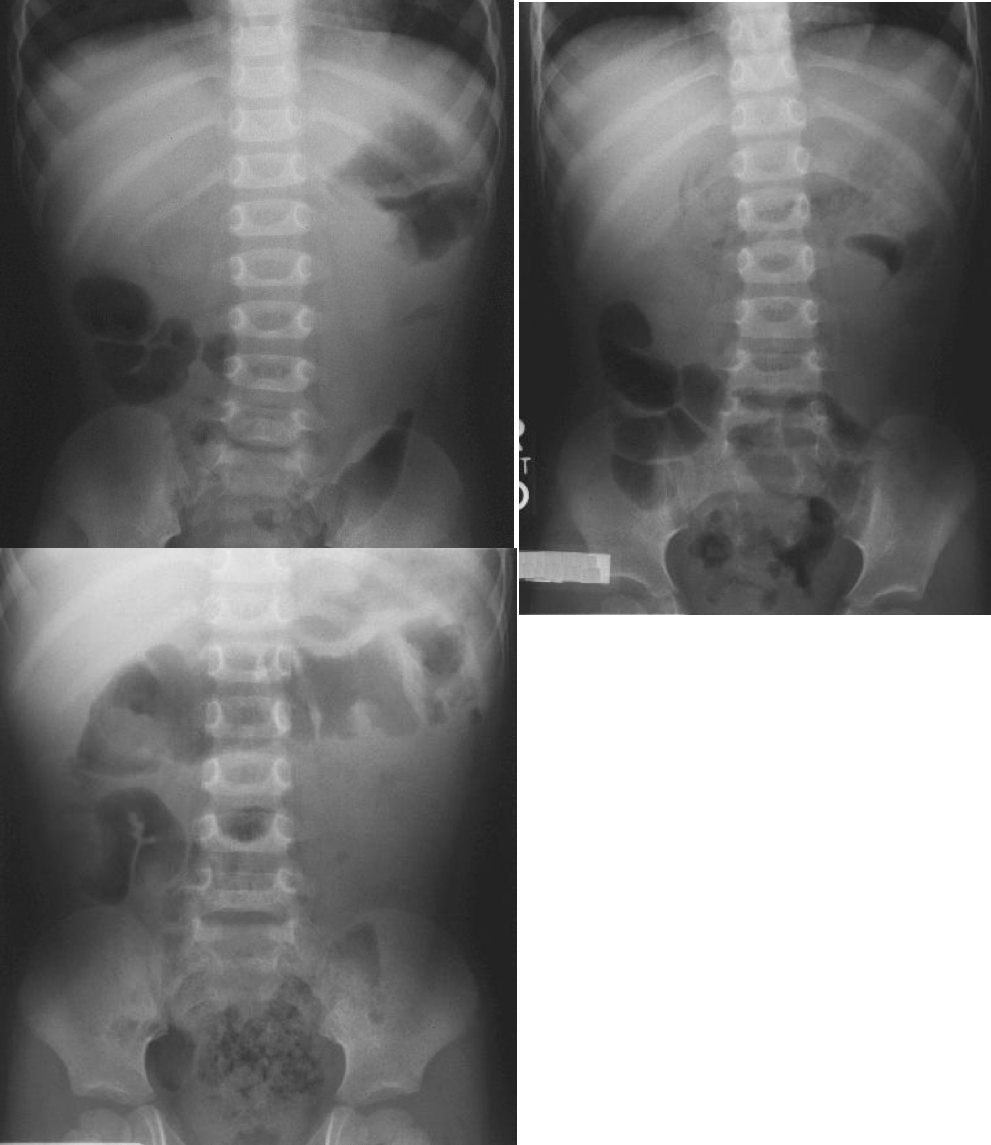

• Signs of intussusception on plain film:

• Target sign

• This radiograph shows a classic target sign in the right upper quadrant just below the liver. It resembles a chubby doughnut with a puffy center. It is very subtle. This radiograph also shows the absent liver edge sign and the crescent sign. A paucity of bowel gas is also noted.

• Crescent sign

• Soft-tissue density mass of the intussusceptum projecting into the colon (leading edge). If the head of the intussusceptum is projecting into a gas filled pocket, it will show itself. It often takes on a crescent shape; however, it may also merely resemble a protruding head into a gas filled pocket.

• This radiograph shows a classic crescent sign in the left upper quadrant. This radiograph indicates that the head of the intussuception is in the distal transverse colon. Also note that this radiograph demonstrates the target sign and the absent liver edge sign.

• This radiograph shows an atypical crescent sign in the right upper quadrant just below the liver. The head of the intussusception is coming up the ascending colon. It can be seen protruding upward into the gas filled transverse colon at the hepatic flexure.

• Absent liver edge sign

http: //www.hawaii.edu/medicine/pediatrics/pemxray/v1c02.html

23

Q

Radiographic signs of intussusception on plain film:

A

• Target sign: Two approximately concentric circles of fat density to the right of the spine, due to layers of peritoneal fat surrounding and within the intussusceptum alternating with layers of mucosa and muscle. This sign resembles a very faint target, or bull’s eye, or doughnut appearance.

• Crescent sign: Soft-tissue density mass of the intussusceptum projecting into the colon (leading edge). If the head of the intussusceptum is projecting into a gas filled pocket, it will show itself. It often takes on a crescent shape; however, it may also merely resemble a protruding head into a gas filled pocket.

• Absent liver edge sign: loss of subhepatic angle

• Other non-specific

• Abdominal mass: An absence of bowel gas in the area suggesting indirectly that something is pushing normal bowel out of the way.

• Small bowel obstruction: Dilated bowel loops and air-fluid levels.